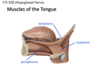

hypoglossal nerve, which provides motor output for the tongue